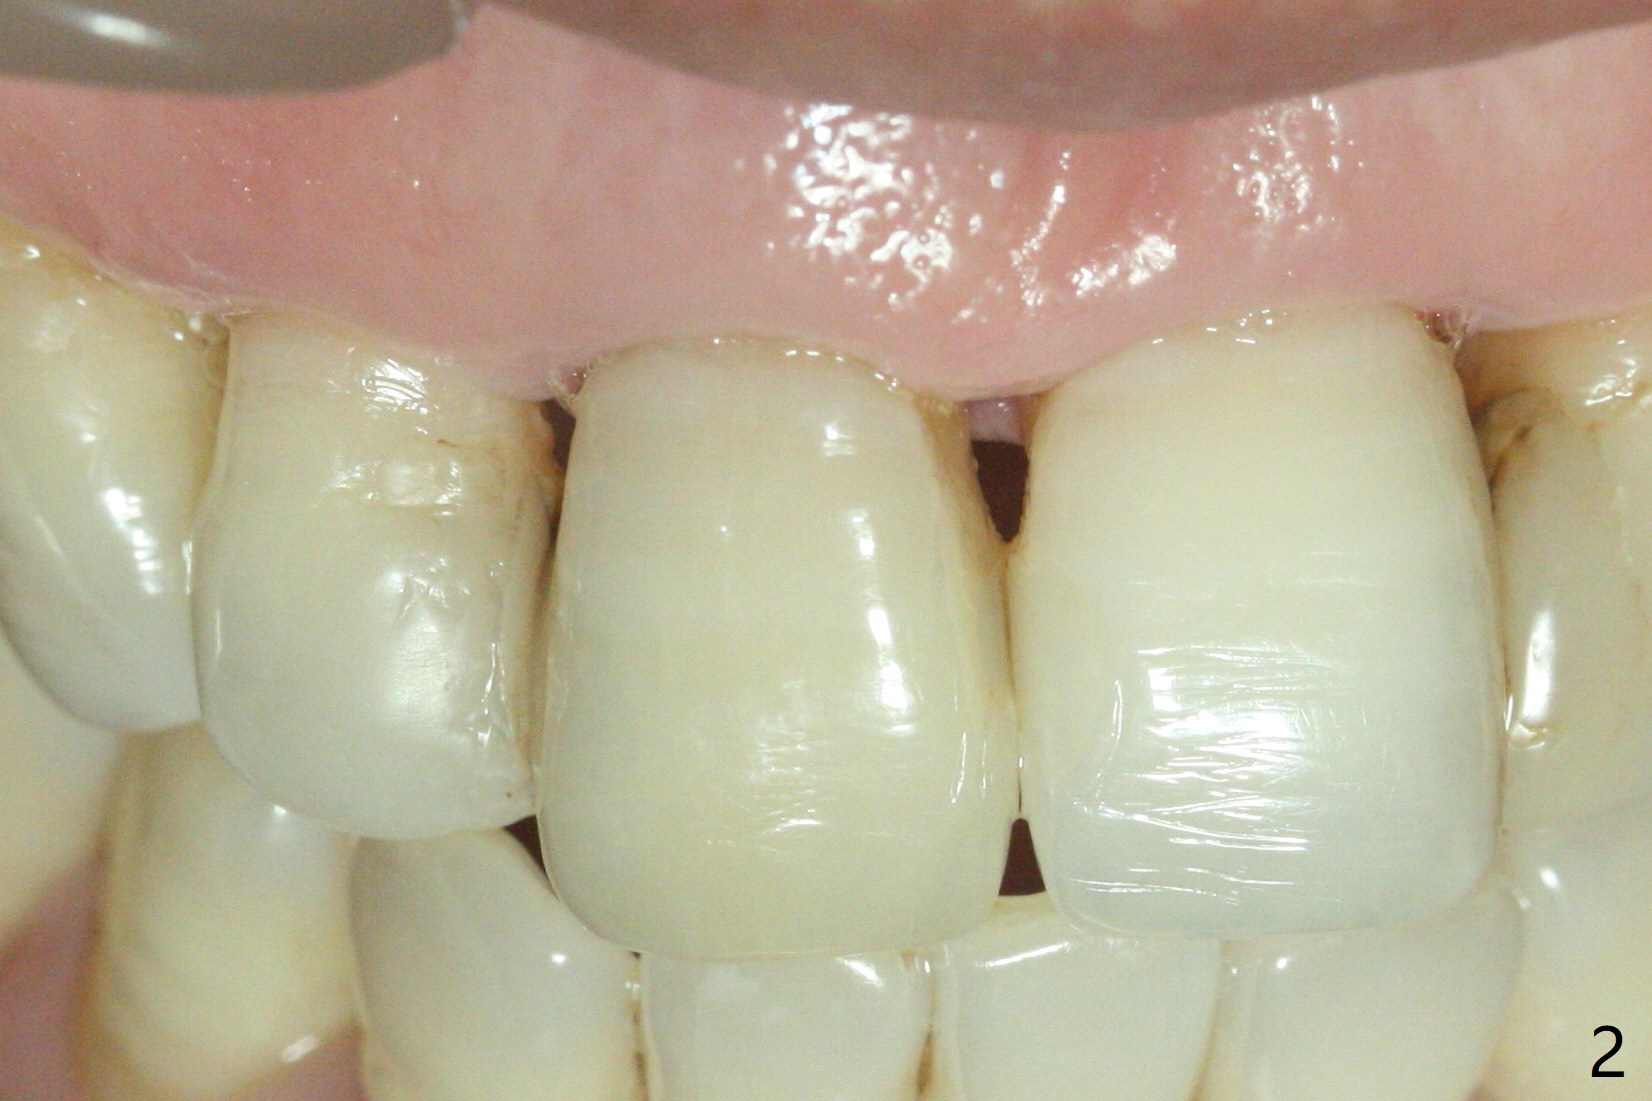

单个门牙变色往往是牙髓坏死所致,根管充填后做漂白,防止漂白泡沫跑到根尖孔之外,这种顺序可以改变吗?53岁女右上1根尖无痛性红肿(图一:^),牙冠变色(图二),牙髓测定:死髓,伴有根尖阴影(图三),中切牙需要根管治疗,什么时候漂白最好,步骤便利?根管治疗后做内漂白,必须把牙胶尖取出,釉牙骨质交界处之下,牙冠长,如这个病例,取出可能困难。我们准备尝试根管治疗当中做漂白,由于死髓牙,根管治疗可以不需要局麻,三个牙齿暴露在橡皮障之外(图四),以便术中漂白观察。根管治疗当中使用大量漂白水,好象并没有改善颜色(图五)。所以在根管口(图六)注入35%双氧水(漂白液,胶状),适当超越釉牙骨质交界处。万一双氧水气泡跑出根尖孔,我们将用生理盐水冲洗,不过这个意外没发生。双氧水也放置在患牙表面(外漂白),两次漂白后(每次20分钟),病人满意牙冠颜色改变(图七)。冲洗,擦干后,在根管中放置氢氧化钙糊剂。预约一个月后完成根管充填,如果牙冠颜色反弹,再次漂白。充填前需要多次冲洗,清除残余双氧水,后者抑制树脂固化。